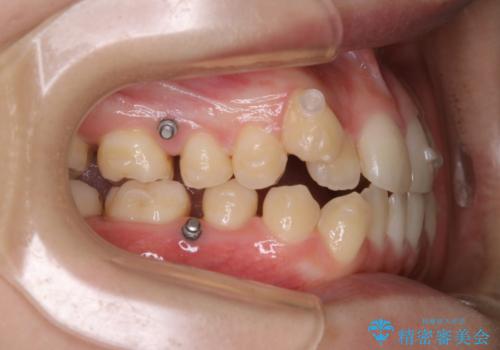

マイクロインプラントと呼ばれる骨に打ち込むネジを使用し、非抜歯での治療計画を立てました。

マイクロインプラントを使用することで非抜歯での治療が可能となりました。

マイクロインプラントを使用せずに無理に非抜歯治療を行った場合、

治療後に出っ歯になってしまうなどの問題が起きる可能性が高いです。